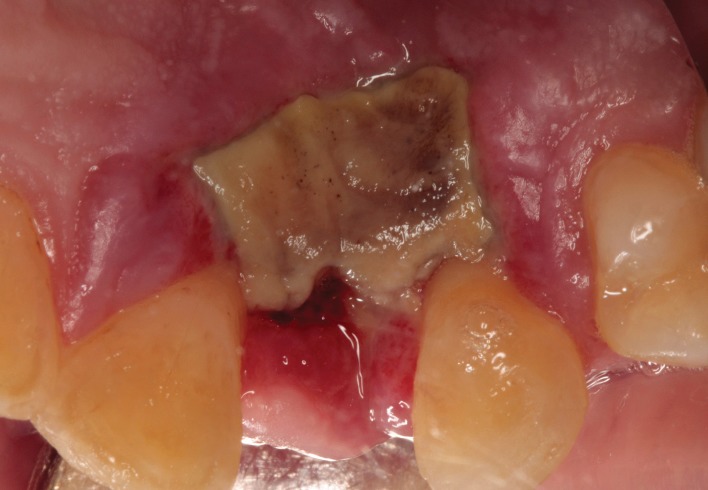

Имплантат был удалён через две недели и два дня после установки. После этого боль и парестезия начали постепенно ослабевать. Однако к концу третьей недели на слизистой оболочке нёба была обнаружена зона некроза (см. рисунок 5), несмотря на то, что нёбный лоскут не отслаивался, а также не проводилась нёбная или резцовая анестезия — то есть, кровоснабжение нёбной области не нарушалось.

Некроз слизистой оболочки неба после удаления дентального имплантата.

Так как повреждение большой нёбной и резцовой артерии и нерва было исключено, некроз нёбной слизистой, появившийся после удаления имплантата, можно объяснить спазмом гладкой мускулатуры сосудистой стенки, вызванным сдавлением сосудисто-нервного пучка. Это привело к временной ишемии тканей и, как следствие, к некрозу. Однако точные сроки появления некроза остаются неясными.